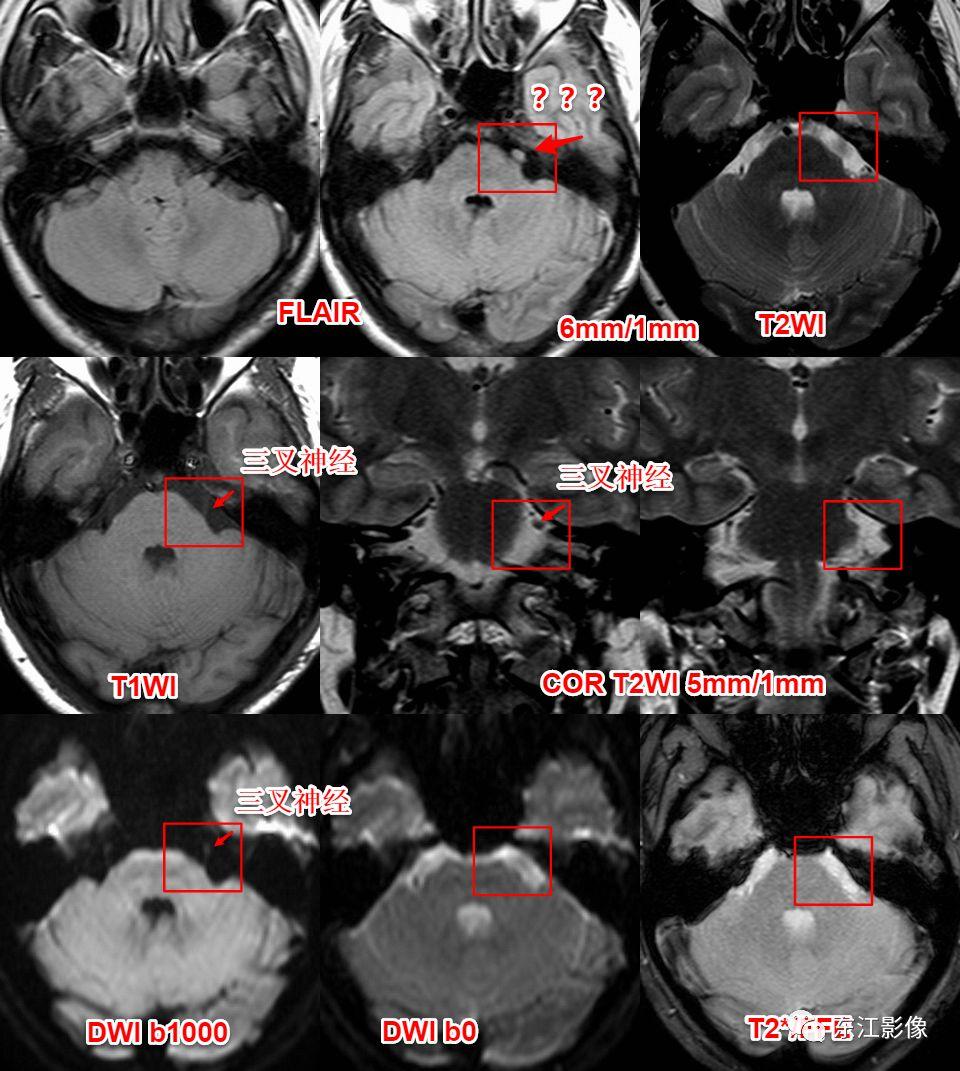

5. 脑脊液流动伪影

- 脑脊液流动伪影主要见于T2WI、FLAIR,主要是长TE序列容易出现流空效应的缘故。

- 但由于脑脊液流动方向、速率不一等因素的影响,呈现为非脑脊液信号影像,部分呈囊样。

- 常见于第三脑室、侧脑室室间孔旁区、脑干周围脑池(这些区域结构复杂)。

- 鉴别要点,T1WI、增强未能辨认;DWI与邻近一致的无信号;无占位效应。

桥前池脑脊液流动伪影。